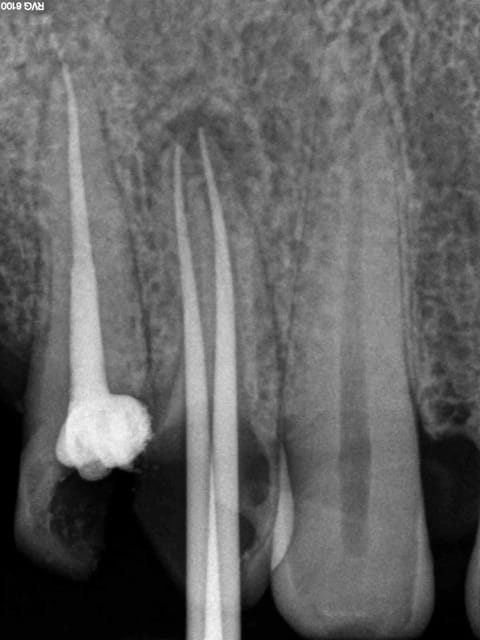

Aujourd'hui patient en urgence ca tombe bien pour une fois synchro avec un lapin.

45 mn de turbinage intensif 2 endos + 2 SC 33; On cote comment les radios ?

Z6, SC 20, Z3,Z3, SC20, Z3, Z3, SC 33, Z3, SC 33, Z3 ?

Tssss, Z6 radio de diagnostic, endo Z3 + Z3 par endo, SC33 radios de controle Z3, 1 par acte.

Avant c'était Z6 par séance quel que soit le nombre de clichés. Je n'ai pas fait les 2 endos en meme temps simplement la première à été faite en mode turbo, j'avais donc du temps en rab et j'ai fait la seconde après. A la limite un Z 3 de trop sur les SC 33.